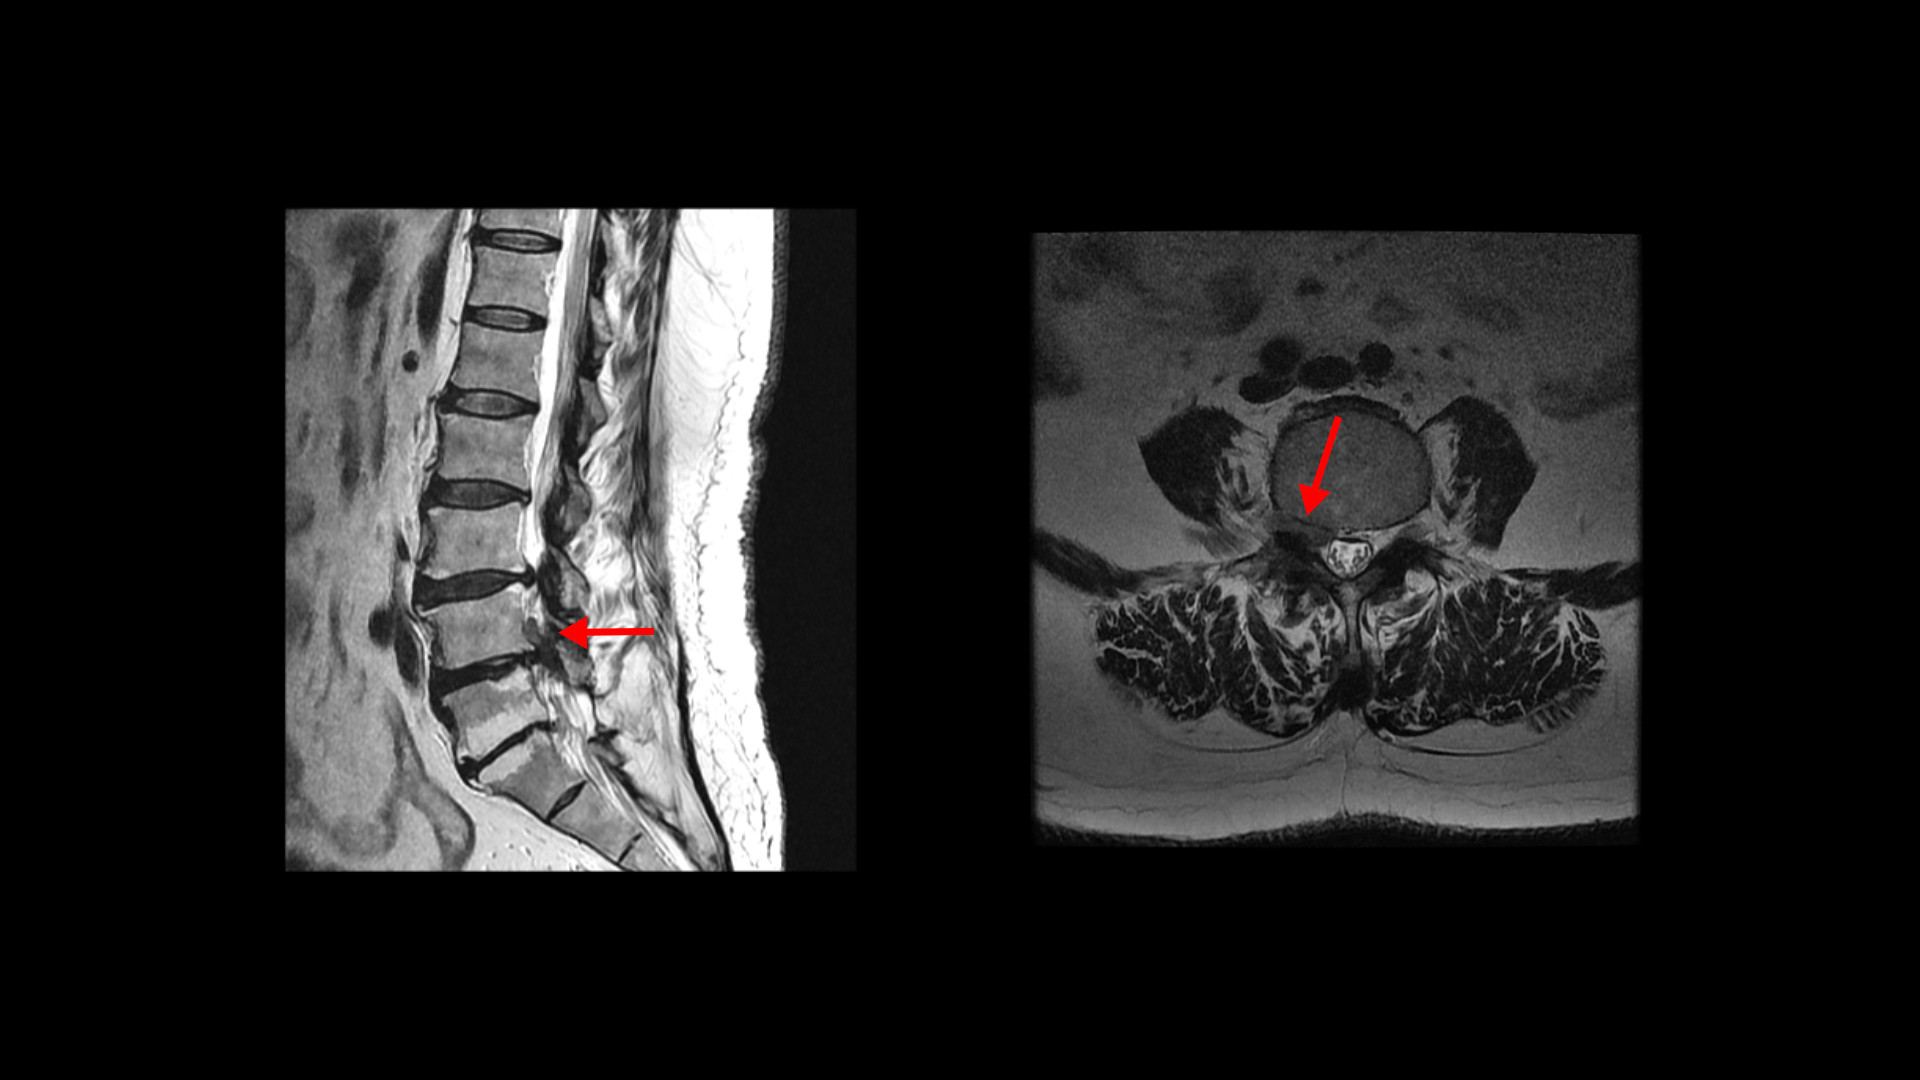

척추수술 후 통증증후군, 척추유합술 후 새로 생긴 방사통과 마비증상을 겪은 환자분의 MRI 상태 및 증상은?

이 환자분은 허리수술을 여러 번 한 상태에서 결국에는 척추유합술까지 하셨습니다. MRI를 보시면 5번 1번 후궁에 수술한 자국이 보입니다.

4번 5번 후궁 양쪽으로 수술한 자국이 보입니다.

올해 초에 4번 5번 디스크가 또 오른쪽으로 심하게 파열돼서 결국 후궁과 후관절, 황색인대를 모두 다 제거하고 나사를 박는 척추유합술을 하셨습니다.

그런데 척추유합술을 하고 난 후 오른쪽 다리의 증상은 호전되었으나 상대적으로 증상이 괜찮았던 왼쪽 다리에 심한 방사통과 마비 증상을 호소하셨습니다. 수술한 병원의 집도의로부터 수술은 잘 됐으나 수술한 자리가 부어있기 때문에 신경을 눌러서 그런 거라고 1년 이상 기다리면 회복될 것이라는 얘기를 들으셨다고 합니다.